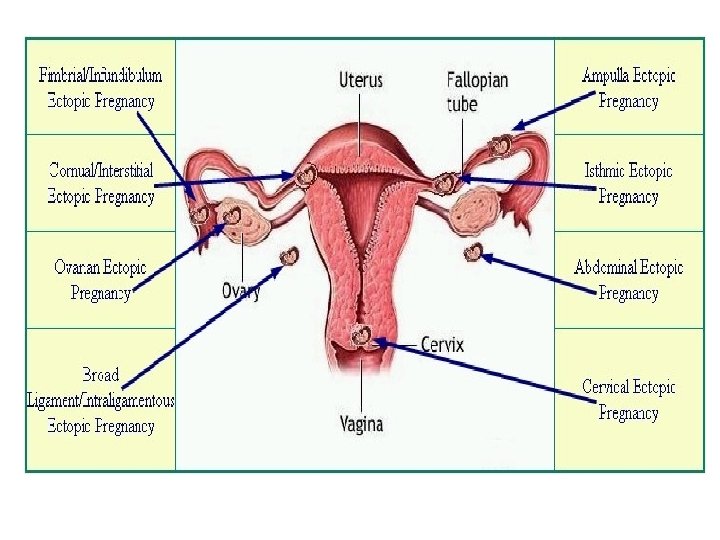

RUPTURE e shtatezanise ektopike:

• Cdo femer ne moshen e fertilitetit qe paraqitet ne urgjence me dhimbje te abdomenit te poshtem duhet te beje TESTIN E SHTATZANISE!!!!!!!